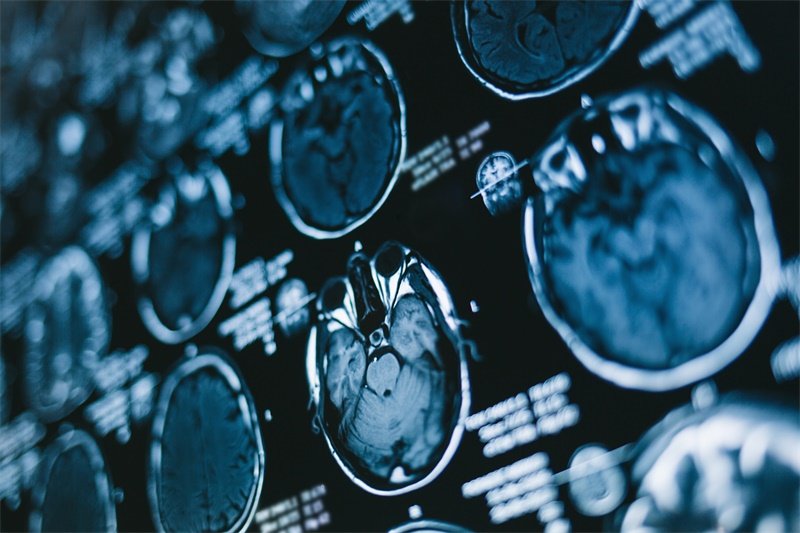

为了有效地检测海马旁回及脑干的占位性病变,临床医生常用的影像学检查手段包括CT和MRI。这些技术能够清晰展示脑部的结构及其病变情况。通过影像学检查,医生可以判断病变的类型、大小及对周围组织的影响。

在检查时,患者需要配合医务人员的安排,确保取得最为准确的影像资料。影像学检查完成后,医生会结合临床表现和病史进行综合分析,从而确诊及制定合理的治疗方案。